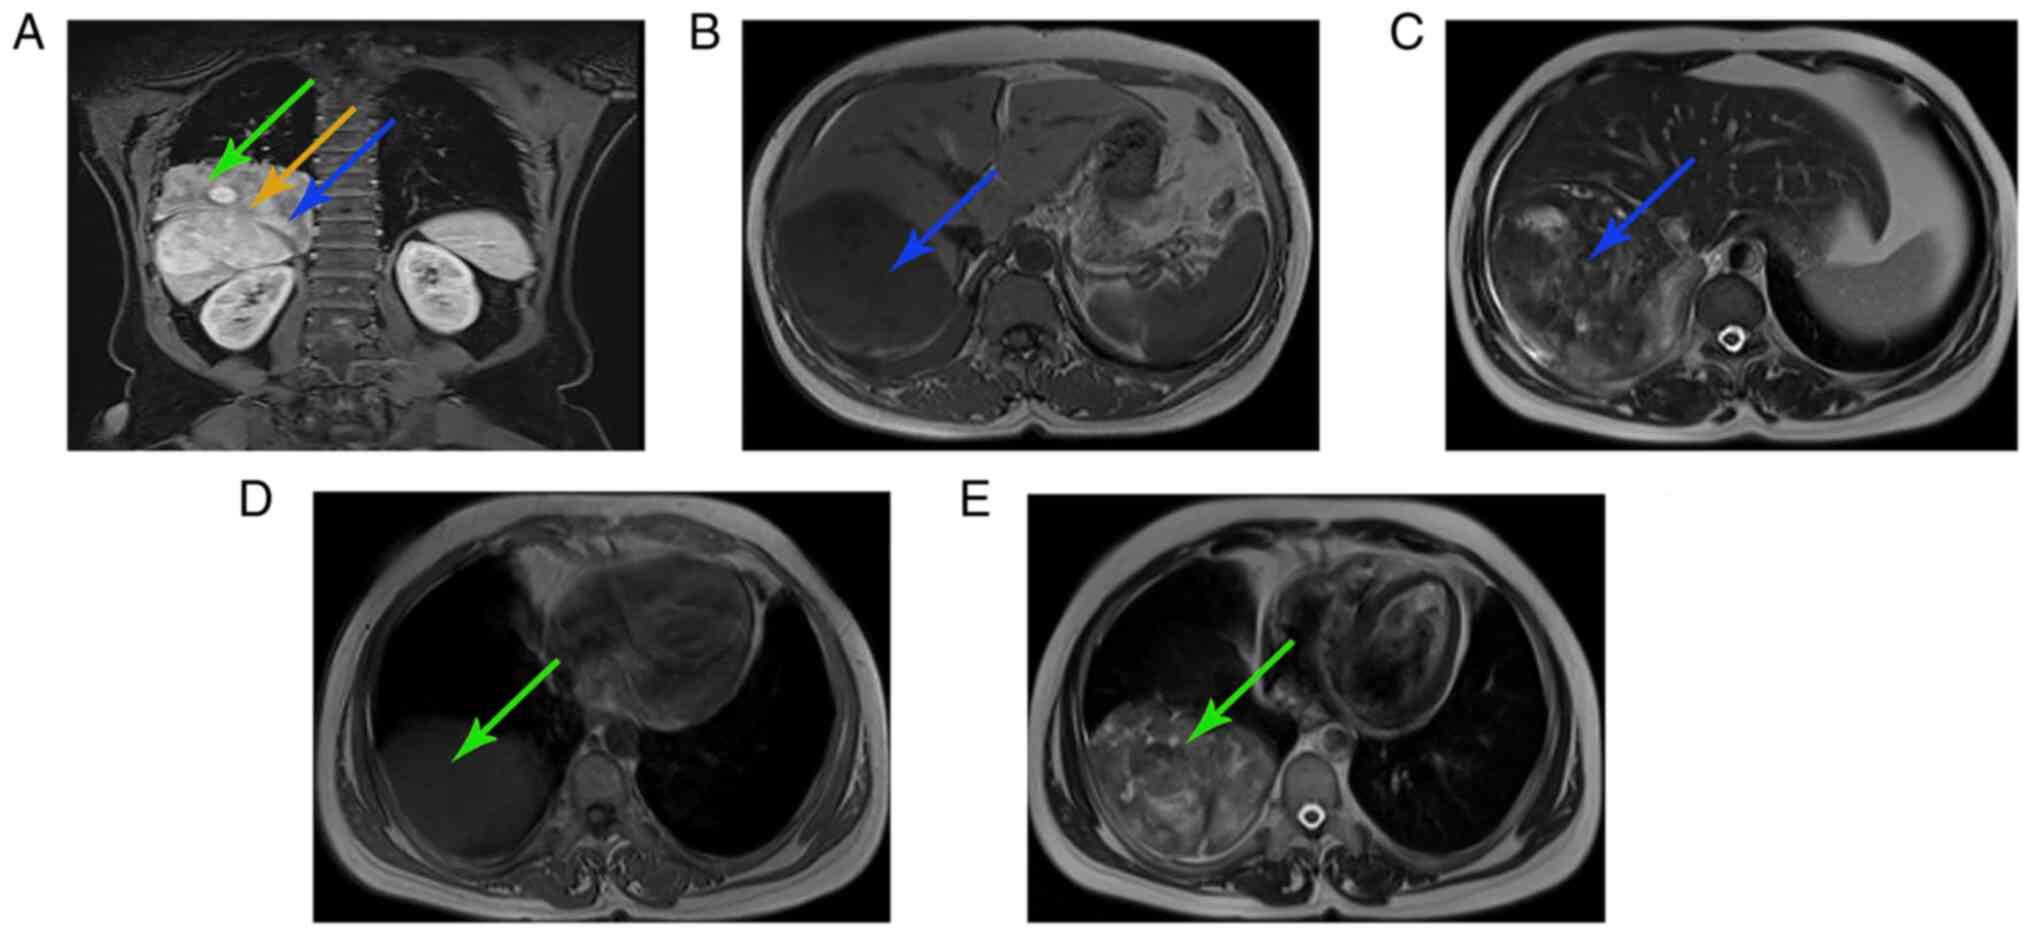

Multidisciplinary collaboration for the successful treatment of a giant hepatic solitary fibrous tumor protruding into the thorax: A case report

Solitary fibrous tumors (SFTs) are composed of spindle cells and collagen fibers, and these form rare mesenchymal tumors. SFTs are most frequently observed in intrathoracic sites; however, they may also occur in extrathoracic sites, such as the liver. Unlike the hepatic SFTs (HSFTs) reported in the literature, the SFT detailed in the present case report was a large tumor that originated from the liver, with a dumbbell‑shaped growth through the diaphragm into the right thoracic cavity. This posed substantial challenges in both diagnosis and treatment. Thus, the present report outlines the findings of a multidisciplinary team meeting that was used to discuss and develop an optimal and personalized treatment strategy for the patient. Transhepatic arterial embolization was performed to block the major arterial blood supply to the tumor in order to reduce its size. Subsequently, the tumor was fully resected, following the collaboration of the experienced hepatobiliary and thoracic surgeons. Following surgery, the abdominal distension experienced by the patient ceased, and no tumor recurrence was detected at the 1‑year follow‑up. In conclusion, due to limited previous reports of HSFT treatment using multidisciplinary collaboration, the present study outlined the treatment used for this specific tumor type, and the corresponding literature was reviewed.